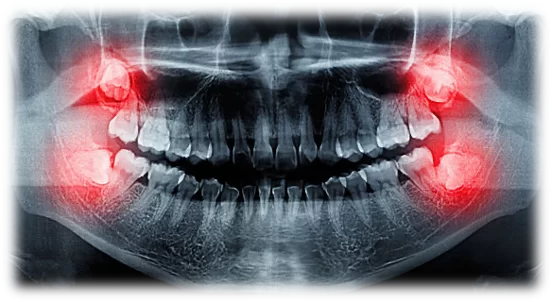

| Nhổ răng thường | 1.000.000 – 1.500.000 / 1 răng |

| Nhổ răng thường không sang chấn bằng máy Piezo | 2.200.000 – 3.000.000 / 1 răng |

| Tiểu phẫu răng khôn, răng mọc ngầm bằng máy Piezo | 3.000.000 – 6.000.000 / 1 răng |